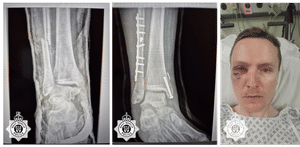

But Richard and Alex Quinn then went further with a cowardly and vicious assault on PC Davis which left him with a dislocated and broken ankle, broken lower leg, multiple fractures and face lacerations including damage to an eye.

The attack left him facing months of trauma during his physical and mental rehabilitation which included multiple operations as he rebuilt his body and his life following the attack.